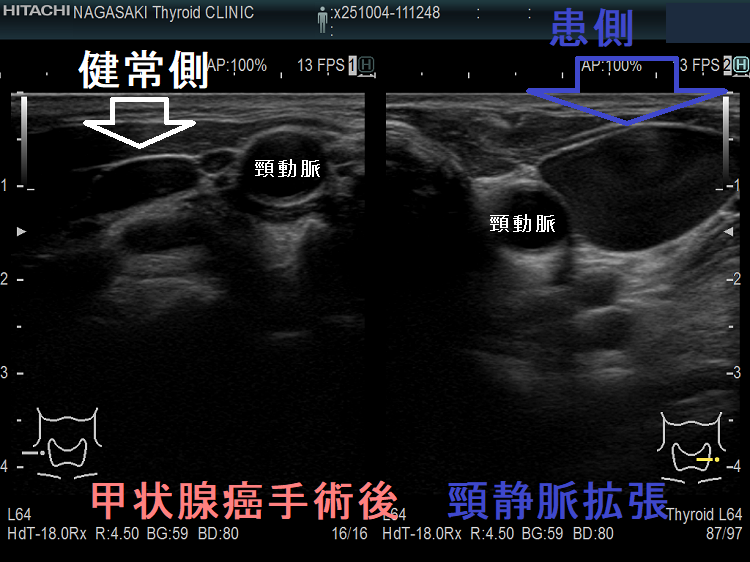

甲状腺癌術後、頸横動脈仮性動脈瘤が生じて破裂する事があります。

報告例は、頚椎後縦靱帯骨化症(OPLL)のため頸部伸展位を取れない状態で外深頸リンパ節を郭清した際、頸横動脈の外膜を傷付け仮性動脈瘤が発生したと推察されます。甲状腺癌手術を終え退院後13日目に頸部痛と左肩甲部から前頸部にかけて腫瘤形成が起きた。画像診断にて頸横動脈瘤とその破裂による大出血と診断し、コ イル塞栓術にて治癒したそうです。(日臨外会誌 67 (10), 2289-2293, 2006)